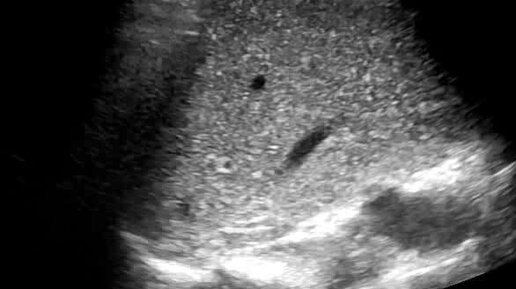

Болезнь Фон-Мейенбурга. Сканирование конвексным датчиком

Ультразвуковые находки от врача УЗД Зорина Я.П.